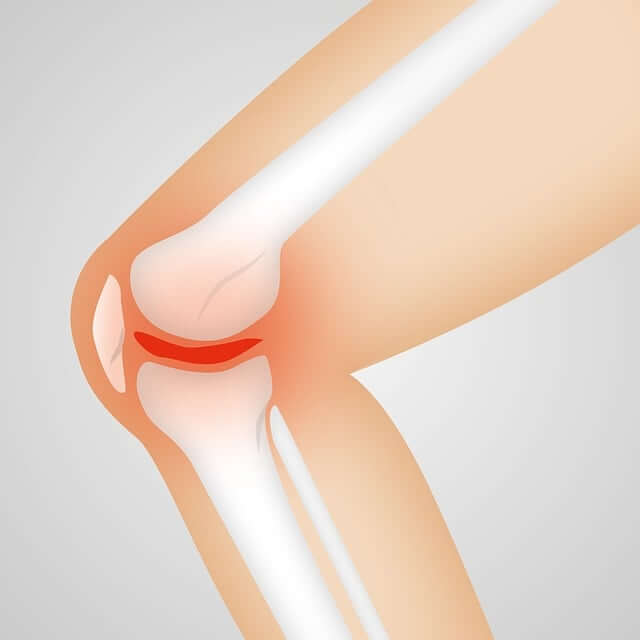

무릎은 우리 몸에서 가장 큰 관절 중 하나이며, 다리를 움직이는 데 중요한 역할을 합니다. 무릎은 다리뼈인 대퇴골과 종아리뼈인 족골을 이어주는 관절로, 이를 통해 다리를 움직이는 근육과 인대를 연결합니다. 또한 무릎은 인체의 몸무게를 지탱하고 충격을 흡수하는 기능도 담당합니다.

슬관절염은 슬관절 주변의 연골 파손 및 염증으로 인해 발생하는 관절염입니다. 이는 보통 연령이 들어갈수록 발생할 가능성이 높아지며, 통증, 강직성, 염증, 운동 장애 등의 증상을 유발할 수 있습니다.

무릎 관절연골은 무릎 관절을 보호하는 역할을 합니다. 무릎 관절연골에 손상이 생기면 통증, 부종, 운동 장애 등의 증상이 나타날 수 있습니다.

나이가 들면서 무릎 관절에 염증과 마찰이 생기는 것이 자연스러운 일입니다. 이러한 마찰은 무릎 통증, 강직성 등의 증상을 유발할 수 있습니다.